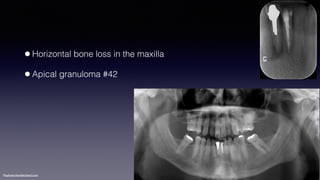

•Horizontal bone loss in the maxilla

•Apical granuloma #42

©sylvainchamberland.com